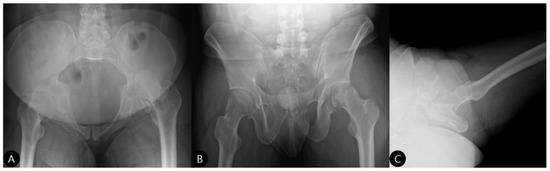

- Exposure and Assessment: The hip joint was exposed. The femoral head was found to be dislocated posteriorly. The posterior wall was severely comminuted into six small, non-viable osteochondral fragments (Figure 3), confirming the impossibility of anatomical reduction and stable fragment fixation.

- 3 Months: Radiographs showed a stable hip construct with no signs of subluxation or screw migration (Figure 7). The patient had returned to activities of daily living without major discomfort. The mHHS was 78/100.